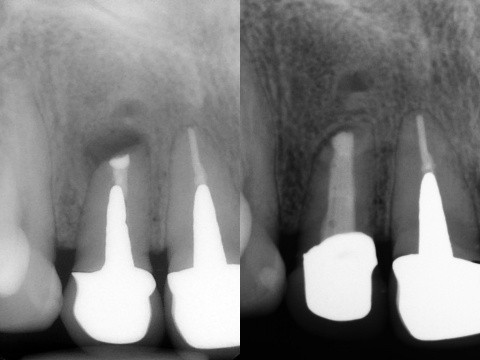

言葉で書くのは簡単ですが、これには非常に時間がかかりとても困難な治療でした。そこにMTAセメントを用い、根の先端の方(赤矢印)と吸収部(黄色矢印)を同時に埋めました。

黄色矢印の左の方を見ていただくとわかると思いますが、外にはみ出しているのがわかるかと思います。

これはMTAセメントを押し込んで、わざとはみ出しています。

この後歯茎を開いて、はみ出したMTAセメントと除去しきれていない外部吸収部を除去して、グラスアイオノマーというセメントにより同部を埋めました(赤矢印)。

これも言葉にして書くと簡単なのですが、これをピッタリ埋めるのが非常に難しかったです。